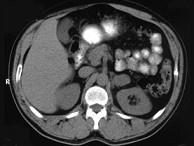

问题 女,34岁,无意中发现血压升高4个月就诊,行CT检查,如图所示,下列说法正确的是 ( )

选项 A、考虑为左肾上腺嗜铬细胞瘤 B、考虑为左肾上腺转移瘤 C、增强扫描,该病灶周边明显强化,中心处强化不明显 D、考虑为左肾上腺腺瘤 E、CT示左侧肾上腺区可见一等密度块影,边界清楚

答案 ACE